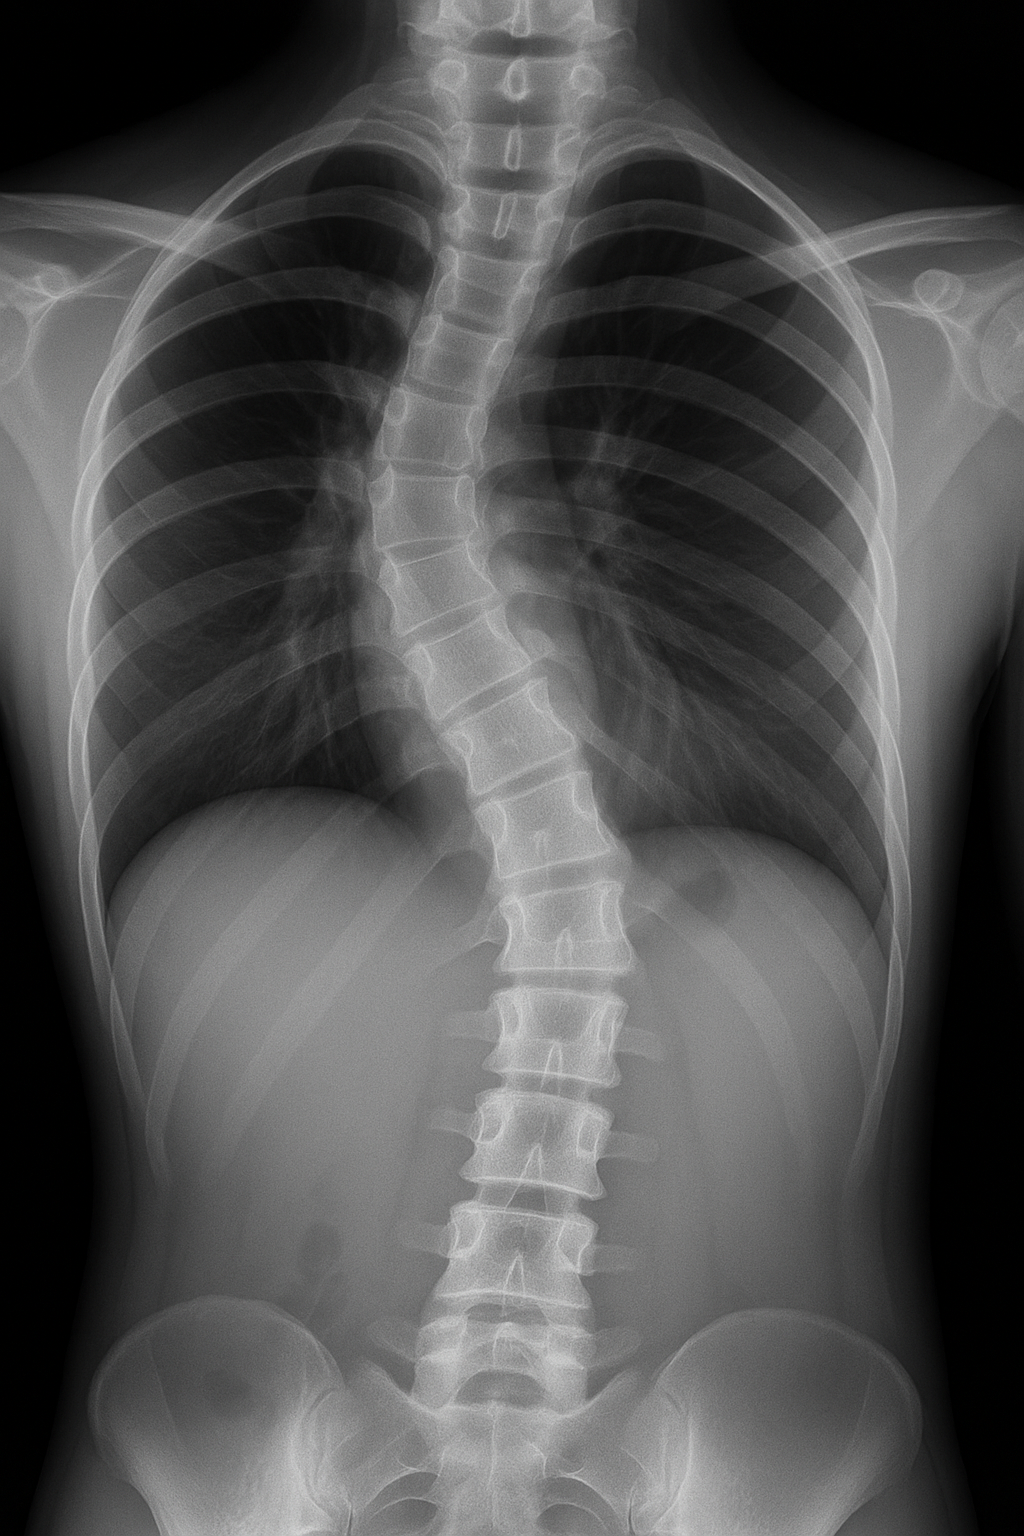

안녕하세요. 저는 흉추 측만증을 가지고 있는 20대 청년입니다. 현재 저의 흉추는 오른쪽으로 13도가량 휘어진 상태입니다. 고등학교 3학년 겨울에 측만증 판정을 받았었고 이미 성장판은 닫히고 말랑말랑했던 뼈는 단단해져서 변화를 바라기에는 늦은 시기였습니다. 공식적으로 병원에서 측만증 판정을 받을 당시에 흉추가 틀어진 것뿐만 아니라 몸의 축도 살짝 돌아가고 골반의 좌우 높낮이도 달라져 온몸이 틀어진 상태였습니다. 원인은 불명이라 하셨고 저는 평소에 자세도 바른편이었고 운동도 좋아해서 활동량이 많았는데 저에게 측만증이 생겼다는 사실에 충격에 빠졌었습니다. 갑자기 후천적으로 나타나는 경우도 있다고 하시면서 의사 선생님은 저는 휘어진 정도가 비교적 경미 한 편이라 흉추가 휘어지면서 갈비뼈가 장기를 누르진 않아 폐나 심장 쪽에는 영향을 미치지는 않을 거라고 판단하고 수술까지는 추천하시지 않으셨습니다. 그럼에도 제 몸의 틀어짐을 매 순간마다 느끼고 싶지 않아도 온몸으로 느끼고 있었고 대책이 필요했고 저의 일상에 변화가 생기기 시작했습니다. 인터넷, 병원, 헬스장 이곳저곳에서 치료법에 관해서 알아본결과, 측만증은 현실적으로 청소년이 아닌 이상 드라마틱한 변화를 바라기 어렵고 수술은 리스크가 너무 컸고 그저 상황이 더 이상 악화되지 않게 하는 것이 최선의 방법이라는 내용이 많았습니다. 가능성에 대해서만 언급하고 확신의 단어는 보이지 않았습니다. 그래서 평소 운동을 좋아했던 저는 어렸을 때 수영, 복싱 등 다양한 운동을 접했었고 병원이나 물리치료센터에서 교정치료를 받는 것보다 내가 내 몸을 연구해서 나 스스로 교정을 해보기로 했습니다. 여러 가지 스트레칭을 해보고 나름 고안해서 생각해 낸 새로운 동작을 내 몸에 적용시켜 보고 내 몸이 어떻게 움직여지는지 많은 시도를 했습니다. 어떠한 동작을 하든 바른 자세로 허리에 무리가 가지 않는 자세를 만들려 노력했고 걸음걸이는 앞쪽으로 쏠리는 자세가 아닌 뒤꿈치부터 발중간, 발끝 순으로 발을 내딛는 연습도 했습니다. 그래서 무언가를 집는 행위, 걷는 행위 앉는 동작, 가방을 어디 쪽으로 먼저 메는지, 바지를 입을 때 왼쪽 발부터 계속 먼저 넣지는 않는지, 가만히 있다가 앞으로 걸어갈 때 어느 발부터 나가는지 등등 거의 강박에 가깝게 몸의 대칭을 맞추려 하면서 정작 내가 해야 할 일에도 집중을 못할 정도에 이르러 한동안 지금 내가 하고 있는 게 맞나 의심이 들면서 회의감에 빠져 하루하루를 살아가고 있었습니다. 어디까지나 '측만증'이라는 주제에 대해서 제 이야기를 할 뿐 다른 의미는 없습니다. 이런 사람도 있구나 하면서 봐주시면 감사하겠습니다.